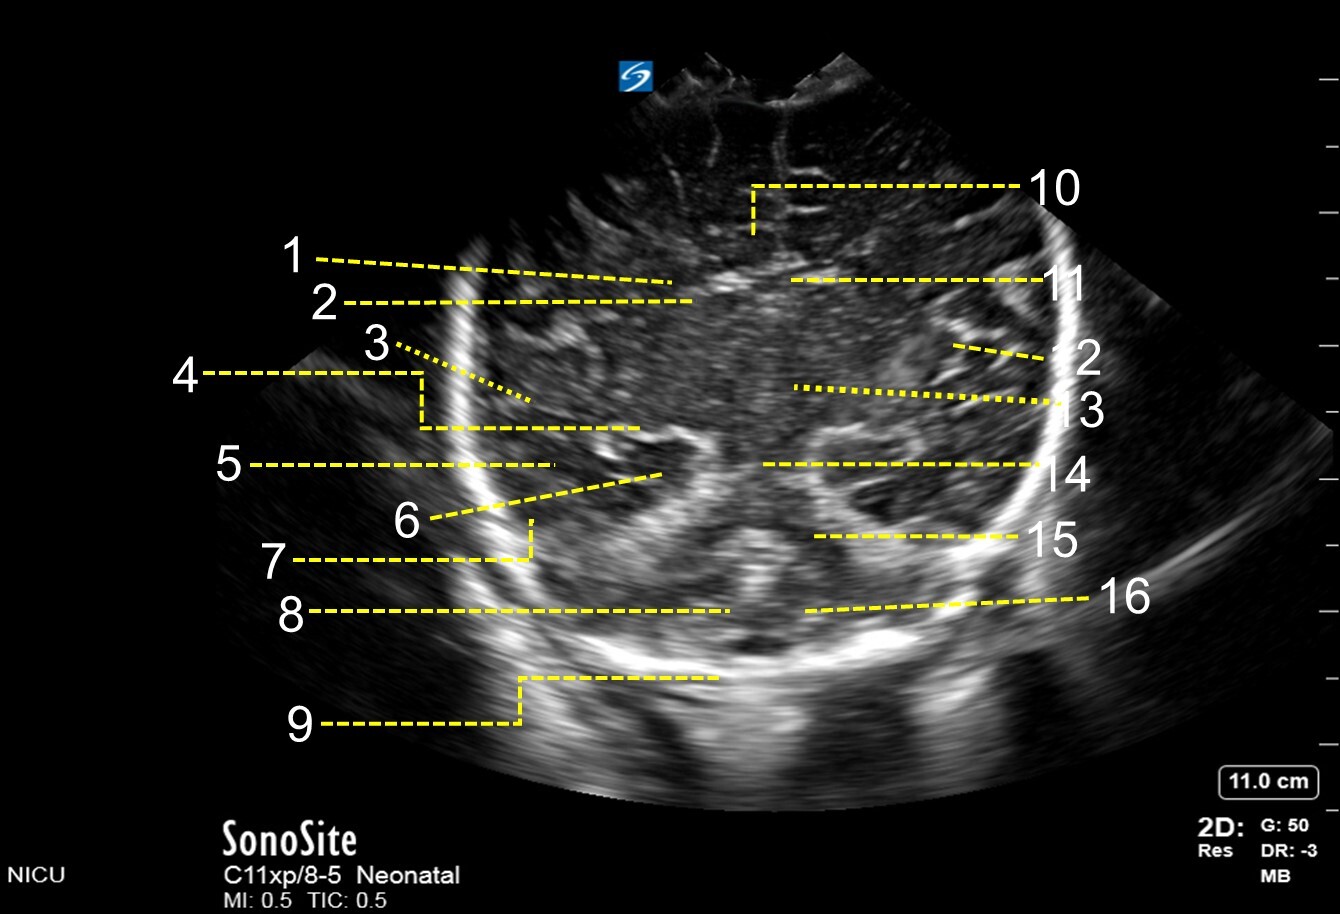

1. Choroid Plexus

2. Caudate Nucleus

3. Parietal Lobe

4. Basal Ganglia

5. Temporal Horn of Lateral Ventricle

6. Para Hippocampal Gyrus

7. Temporal Lobe

8. Cerebellar Vermis

9. Skull Frontal horn of Lateral Ventricle

10. Inter Hemispheric Fissure

11. Corpus Callosum

12. Sylvian Fissure

13. Thalamus

14. Mesencephalon

15. Tentorial Area

16. Cerebellar Hemisphere